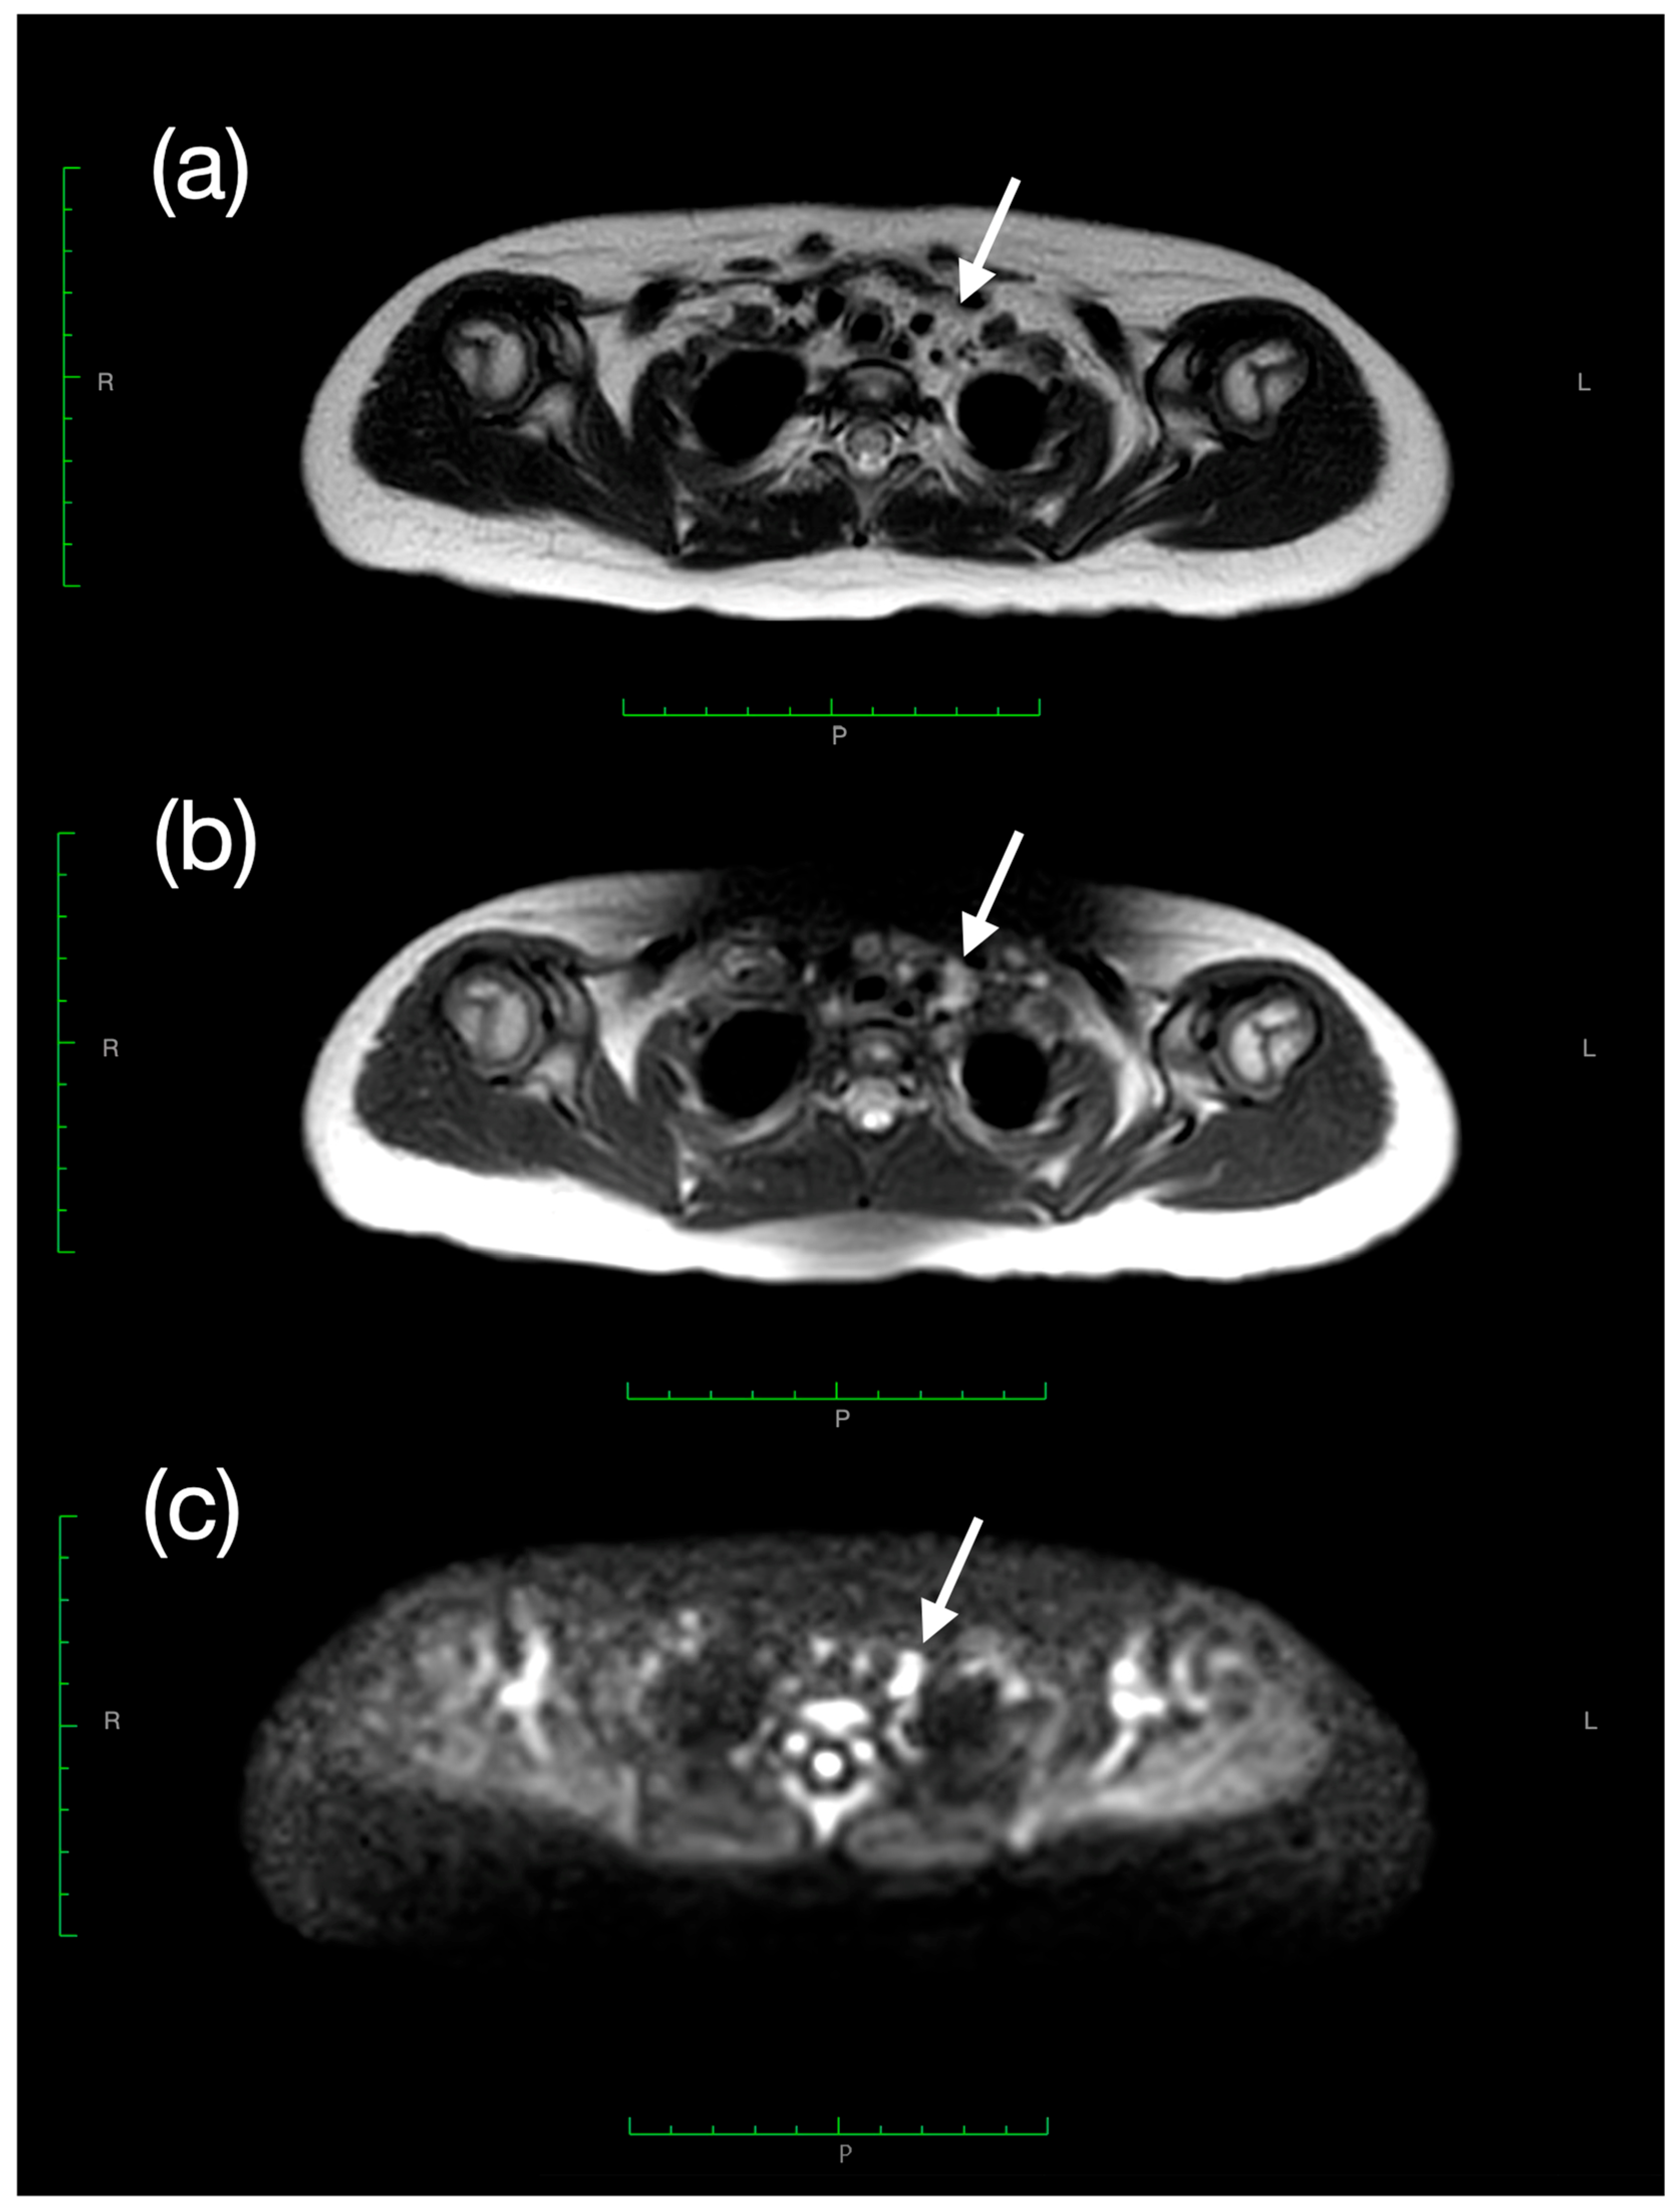

2. Case Presentation